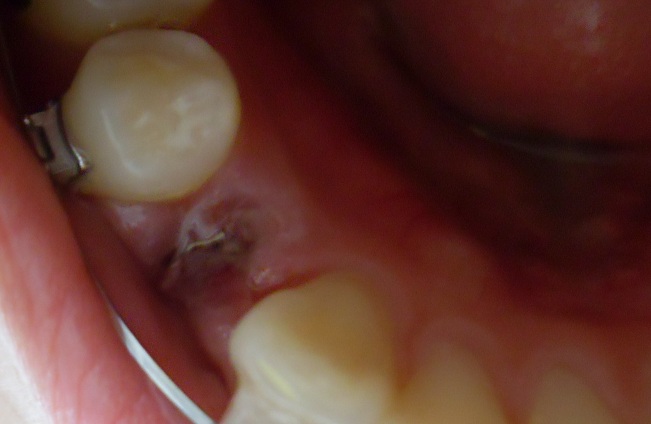

오라픽스 포스팅 사진 (4).JPG

양쪽에 이렇게 이가 없으니

오라픽스 포스팅 사진 (2).jpg

교정하구 첨으로 죽을 먹엇네요ㅋㅋㅋㅋㅋㅋ

이 때는 왼쪽도 치아 발치한 상태라 음식을 먹을 때 너무 조심스러웠어요.